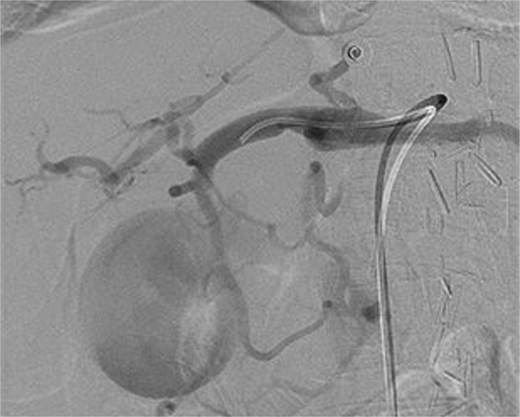

A computed tomography (CT) of the abdomen with IV portal venous contrast demonstrated proximal gastric dilatation due to a 7.6 cm gastric pyloric mass concerning for malignancy (Fig. 1). Other findings included small volume pancreatic parenchymal calcifications with no ductal dilatation. She was decompressed via nasogastric tube and planned for gastroscopy and feeding tube insertion. Gastroscopy demonstrated a partially obstructing extraluminal mass at the gastric antrum, able to be traversed to the second part of the duodenum (Fig. 2). A nasojejunal feeding tube was placed and the nasogastric tube was left in for decompression. An endoscopic ultrasound the following day demonstrated Doppler signal in the mass, confirmed to be a large 6.2 × 4.2 × 7.0 cm pseudoaneurysm arising from the GDA on a subsequent CT mesenteric angiogram (Fig. 3). Coil angioembolization of the pseudoaneurysm was successfully done via common femoral access (Fig. 4). She was commenced on NJ feeding and supplemental parenteral nutrition. She recovered well and was discharged on puree diet. Repeat imaging at 4 weeks demonstrated resolution of the pseudoaneurysm and returned to normal diet 6 weeks post presentation.

Intraoperative photograph of successful coil angioembolization of the pseudoaneurysm.